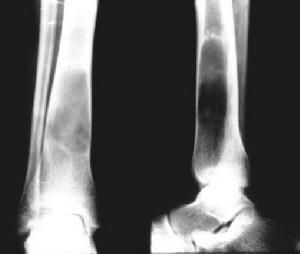

單房性骨囊腫診斷本症的診斷主要靠X線檢查和病理活檢。X線照片上顯示骨幹部中心性大透亮區有助於診斷。局部骨皮質變薄,體積略有膨脹。

X線檢查:囊腫一般位於長管狀骨的一端,局部骨幹的骨皮質略向外膨脹囊與骺板之間尚間隔有一小段松質骨。囊腫距骺板的遠近依病變發生時間的久暫和範圍而定。偶見囊腫穿透骺板進入骨骺如發生骨折,囊腫與骺板之間的松質骨可發生變形,但骨折多無移位